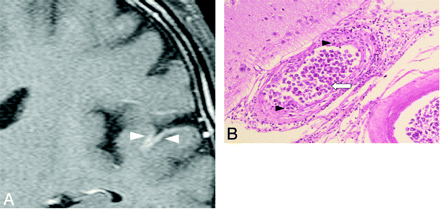

Case 2. Meningeal enhancement in a 69-year-old man. A, Gadolinium-enhanced coronal T1-weighted image shows abnormal meningeal enhancement around the temporal lobe before treatment (white arrowheads). B, Pathologic specimen shows thickening of the affected vessel walls with intraluminal (white arrow) and subendothelial (black arrowheads) tumoral infiltration (hematoxylin-eosin, original magnification ×25).

Meningeal enhancement was observed in 2 patients (Fig 3A). In 1 of 2 patients with meningeal enhancement, the enhancement decreased just after treatment started. No surrounding edema or intraparenchymal enhanced lesions were observed. Postmortem examination revealed thickened vascular walls and necrotic and subendothelial tumor infiltration with abundant lymphocytes surrounding the vascular walls (Fig 3B). Masslike lesions were observed in 1 patient with multiple intraparenchymal focal enhanced lesions and mass effect (Fig 4A). No abnormal findings were found on DWI (Fig 4B). A gradual decrease in the contrast enhancement and mass effect of the lesions was observed after chemotherapy was started (Fig 4C). No postmortem examination was performed on this patient. The hyperintense lesions in the pons on T2WI without diffusion restriction or contrast enhancement were observed in 5 of 11 patients. This signal-intensity pattern was the only abnormal one in 4 of the 5 patients. All 5 patients showed symmetric hyperintense areas in the central pons, sparing the pontine tegmentum and ventrolateral pons (Fig 5A). The hyperintense areas in the pons decreased in size and intensity in all of the 4 patients treated (Fig 5B). In case 9, a follow-up MR imaging showed a decrease in the size of the lesion 3 days after treatment. Brain stem atrophy was not observed in any of these 4 cases after treatment.